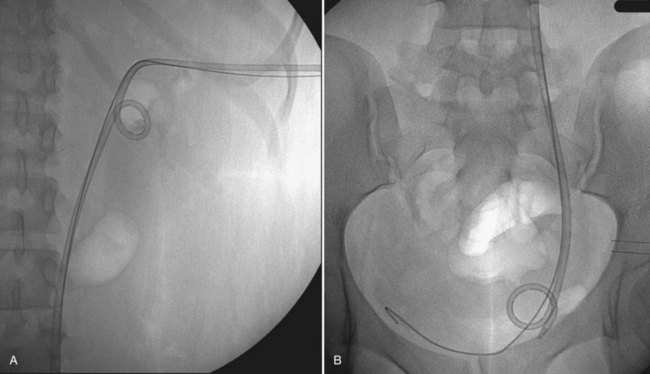

), and a guidewire can be passed from below and grasped by the nephroscope to establish through-and-through access from the external urethral meatus to the percutaneous entry site. A dual-lumen catheter can be placed as well. The small caliber of either catheter, however, does not provide much outflow from the kidney and may not prevent stone or tumor fragments from passing into the ureter along the catheter. A ureteral occlusion balloon catheter, which incorporates an approximately 15-Fr spherical balloon on the distal tip, more consistently prevents material from migrating down the ureter. The balloon should be carefully inflated in the renal pelvis, making sure the balloon is not in the ureter—which could lead to ureteral rupture—and then gently pull down to occlude the ureteropelvic junction (Fig. 47–12). Another alternative is to place a ureteral access sheath (usually 11 to 15 Fr) over a retrograde-inserted guidewire (Landman et al, 2003). The large outer diameter of the sheath effectively prevents particles from passing around the sheath into the ureter, and the large inner diameter affords excellent outflow of small stone particles. The disadvantages of employing a ureteral access sheath include the potential ureteral trauma from passing such a large device into the ureter and clogging of the catheter lumen by oversized stone fragments.

Figure 47–12 Occlusion balloon inflated and snugged down at ureteropelvic junction of contrast-filled upper tract collecting system.